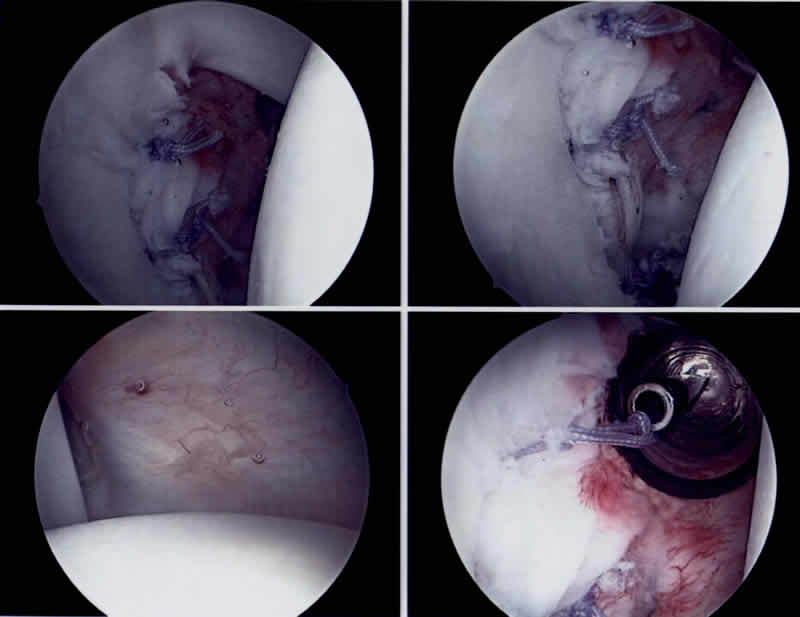

Das Schultergelenk ist das beweglichste Gelenk des Menschen. Dies ist möglich, weil die Schulter nur eine geringe knöcherne Führung mit relativ kleiner Gelenkpfanne hat. Der im Vergleich zur Gelenkpfanne wesentlich grössere Kopf „hängt“ in einer durch knorpelige Pfannenrandanteile (Labrum), Kapselbandstrukturen und Muskelgruppen stabilisierten Gelenkkapsel. Aufgrund dieser hohen Beweglichkeit und der sehr „dynamischen Führung“ ist das Schultergelenk jedoch sehr anfällig für Ausrenkungen (sogenannte Luxationen). Diese treten in den allermeisten Fällen aufgrund eines Unfalles auf: Dabei renkt sich der Oberarmkopf fast immer nach vorne und leicht unter die Gelenkpfanne aus und blockiert dort (sog. traumatische ventrocaudale Schulterluxation). Leider sind Patienten bei denen dieses Ereignis sehr früh auftritt, häufiger und öfter betroffen. So kann es bei jungen Patientinnen und Patienten zu wiederholt auftretenden Luxationsereignissen kommen, dies aufgrund eines durch die Erstluxation gesetzten Schadens am vorderen Gelenkpfannenrand. Durch jede weitere Luxation wird nun die vordere Gelenkkapsel deformiert und ausgeleiert, sodass schliesslich dort eine Schwachstelle entsteht. Wenn mehrfach solche Luxationsereignisse auftreten, sprechen wir von Schulterinstabilität des Oberarmkopfes. Diese ist kaum mehr durch Physiotherapie zu heilen. Nur eine Operation kann die verlorene Schultergelenksstabilität zurückgeben. Ob jedoch eine posttraumatische Instabilität des Oberarmkopfes operativ behandelt werden soll, ist abhängig von der subjektiven Störung, von beruflichen Ansprüchen des Betroffenen und dessen sportlichen Freizeitaktivitäten und muss im Gespräch mit dem behandelnden Orthopädischen Chirurgen entschieden werden.

Ziel der Operation ist es, die normale Schultergelenksfunktion weitestgehend durch die Wiederherstellung der normalen Anatomie zu garantieren, was jedoch infolge des unfallbedingten Gewebeverlustes nicht immer möglich ist. Der optimale Zeitpunkt für eine operative Stabilisierung ist der Zustand nach der traumatischen Erstluxation, da dann der anatomische Schaden vergleichsweise am geringsten ist und die zur Heilung notwendigen Gewebebedingungen ideal sind. Wir empfehlen diese Operation vorallem den jungen Patienten und Patientinnen mit häufigen sportlichen Wurfsportaktivitäten (Volleyball, Handball, Basketball, Beach Volleyball, etc.). Diese Operation wird heute unter Berücksichtigung verschiedener Faktoren, fast immer arthroskopisch, das heisst minmal invasiv durchgeführt.